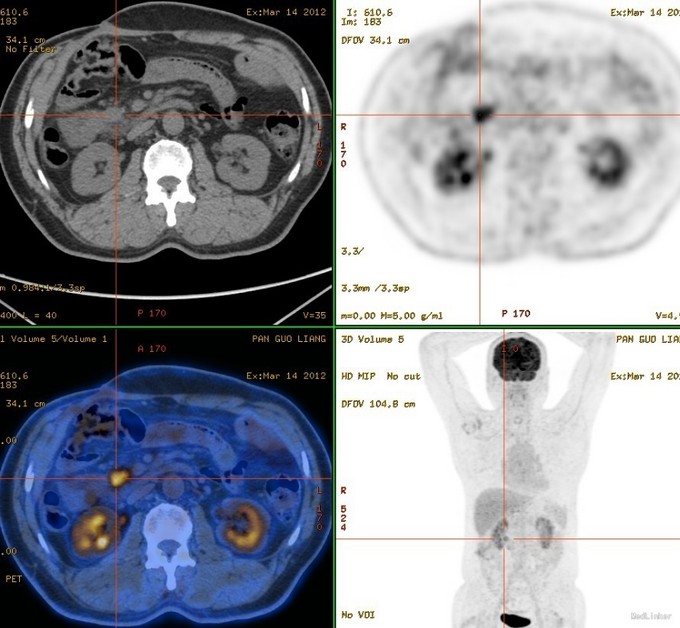

患者老年男性,72岁。以“结肠癌术后4年,烧心伴恶心呕吐6个月”为主诉入院 。现病史:患者2011年7月因肠梗阻急诊于我院行右半结肠ca根治,手术顺利,术后随访。2012年3月PET-CT(图1)提示:十二指肠前方淋巴结,2cm,考虑转移。肿瘤标志物肠癌系列升高。给予患者化疗治疗8个疗程,Xelox方案。患者肠癌系列较前有下降,但未降至正常,腹腔内淋巴结未有明确改变。患者无腹痛腹胀,无恶心呕吐。定期复查。2014-9复查CT(图2):右上腹肠管吻合口形态较前未见明显变化。十二指肠水平段前上方结节较前增大,约3.1cm×3.0cm,边缘模糊,与邻近肠壁及胰头分界不清。考虑肿物较前增大。未特殊处理,增强免疫力治疗。2015-3予以肿瘤科放疗治疗。治疗后,肠癌系列正常。CT:结节较前缩小。放疗后患者出现频繁恶心呕吐,不能进食,呕吐物为唾液,无明显食物,无营养状态下降。行胃镜检查:胃窦部溃疡,1*1cm,无幽门部变形。病理:低分化上皮内瘤变。但患者无烧心,不能除外精神因素呕吐。三个月前予以留置空肠营养管,肠内营养及经口进食。此次再次出现烧心,恶心呕吐,予以耐信口服治疗症状无好转,来诊。既往糖尿病10年。行心脏射频消融手术。